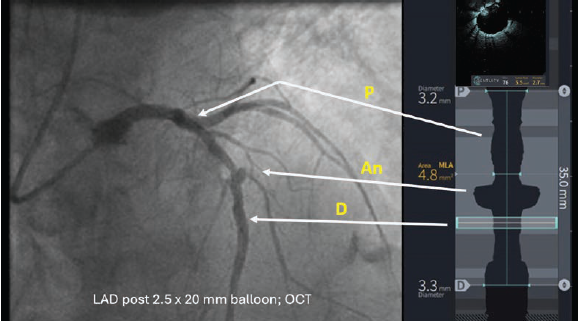

Mort Kern, Long Beach, California: Colleagues, I think I missed the boat on getting an optimal result for a 75-year-old male with a non- ST-elevation myocardial infarction (NSTEMI), high blood pressure and cholesterol, and ETOH abuse. The electrocardiogram showed anterior T wave changes. Elevated troponins (about 2000u) were reported. There was heavy calcification of the right coronary artery (RCA) with only mild disease. The circumflex artery (CFX) had irregularities but no lesions. The left anterior descending (LAD) was also calcified with an 80%-90% stenosis on each side of a large coronary aneurysm about 6 mm in diameter. The PCI was begun with a 2.5 mm x 20 mm balloon, followed by optical coherence tomography (OCT) imaging (Figure 1), then a 3.0 mm x 32 mm drug-eluting stent (DES). OCT showed the free-floating struts and malapposed struts in the proximal segment (Figures 2-3). A 3.5 mm x 15 mm noncompliant balloon just proximal to the stent was used to optimize stent expansion but not applied to the very proximal stent for fear of dissecting the calcific proximal region. Final OCT showed some further stent apposition (Figure 4).

(2) Under expansion in the calcified segment — the minimal lumen area (MLA) is only 4.8 mm2 in the proximal LAD;